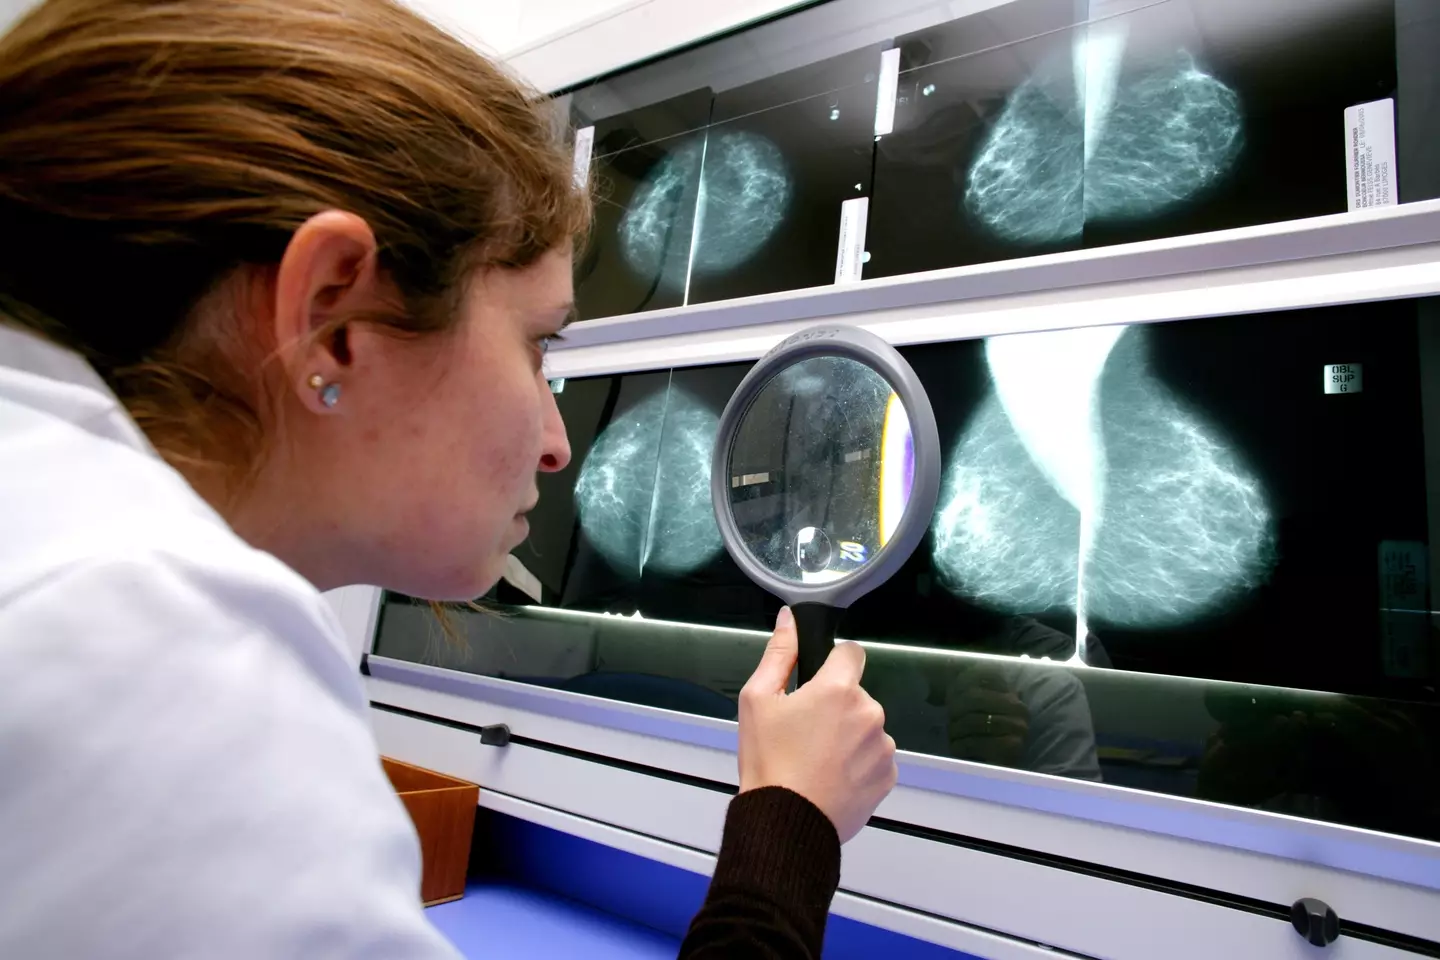

"This technology can look at mammograms and identify areas that a human radiologist may want to look at more carefully.

However, he stressed that while AI had made some impressive advancements, this technology was in place to help human decision-makers rather than outright replace medical professionals.

"One thing humans can do that machines can't do is order special tests. Things like contrast enhanced mammograms and MRIs," Dr Norton said.

"The other thing humans can do is look at previous mammograms and see if there's any changes."

"We've got to think of AI as a tool for helping radiologists look at the images better. It's not a standalone test, it's not gonna replace a radiologist."